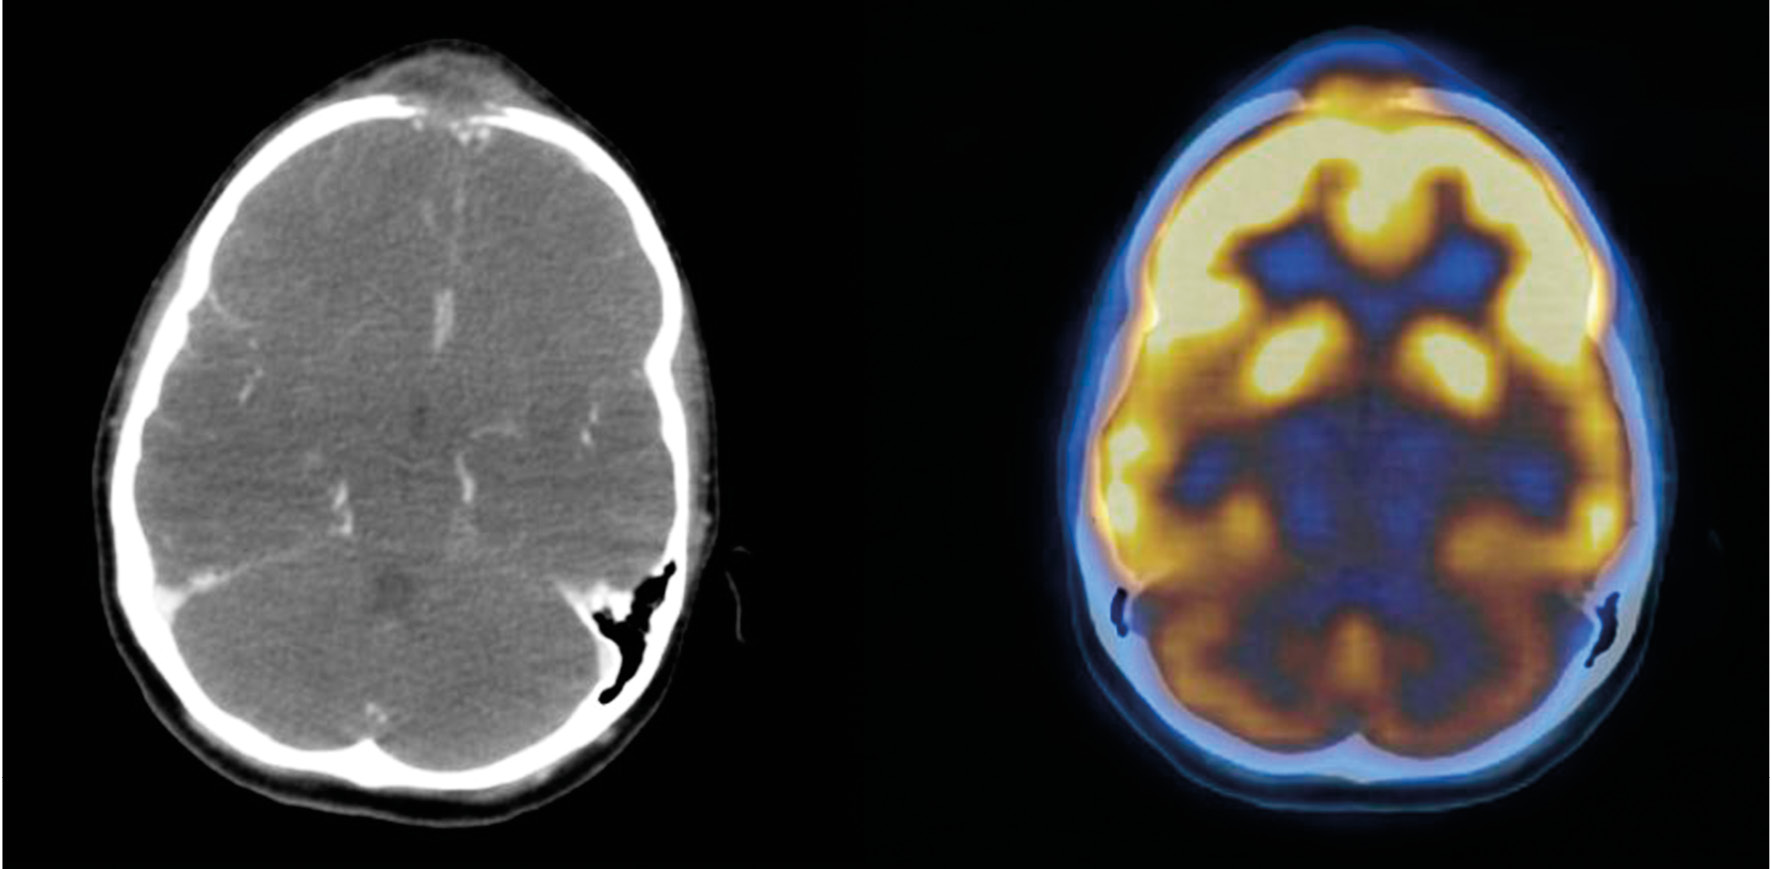

According to the results of the studies, a neoplastic lesion of the frontal bone was suggested. Differential diagnostics was made between lymphoma, plasmocytoma, and sarcoma. In order to search for a primary tumor focus, 18F-FDG PET/CT was performed. In the frontal region, along the midline, an ovoid lesion of 30 × 15 mm in size was revealed, with a significant accumulation of the radiopharmaceutical agent (SUVmax up to 11.2), destruction of the external and internal cortical lamina of the frontal bone (Fig. 6). For the rest of the 18F-FDG foci, no positive neoplastic process was detected; therefore, a widespread metastatic process was ruled out.

Fig. 6. Positron emission tomography with 18F-fluorodeoxyglucose, combined with computed tomography. Left: computed tomography with intravenous contrast enhancement; right: combined image of positron emission and computed tomography. A hypermetabolic focus with destruction of the external and internal cortical lamina of the frontal bone is visible.